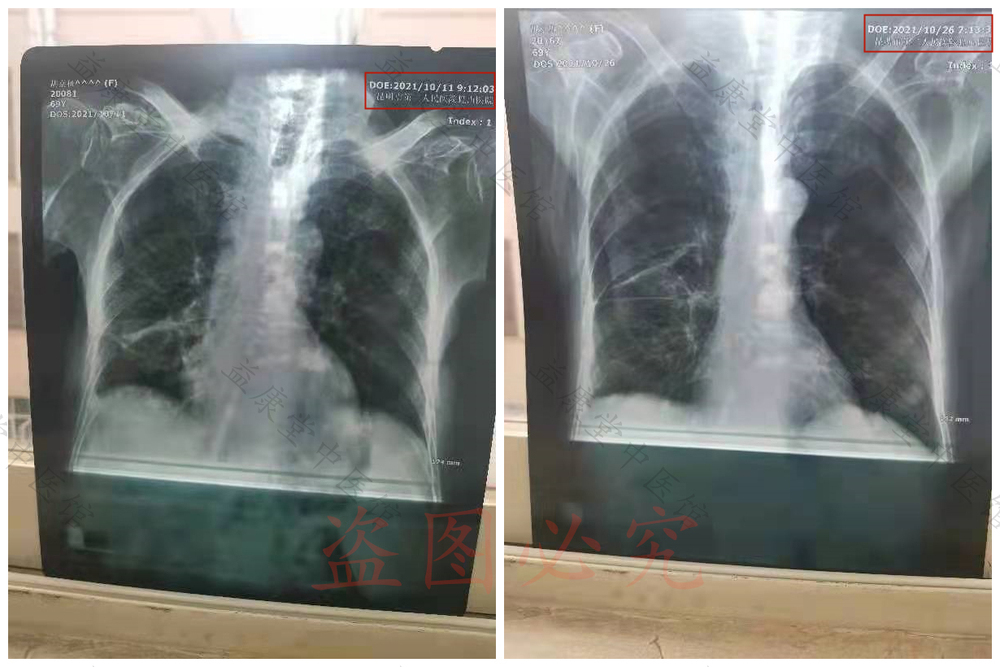

2021年10月11日的胸部CT:肺纹粗糙,右侧肺部下段还有积水。

2021年10月26日胸部CT:右侧肺部下段的积水没有了。